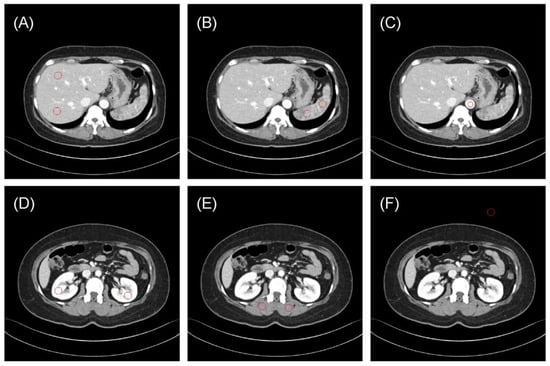

3.1. Region-Based Reproducibility Analysis

3.2. Patient-Based Reproducibility Analysis